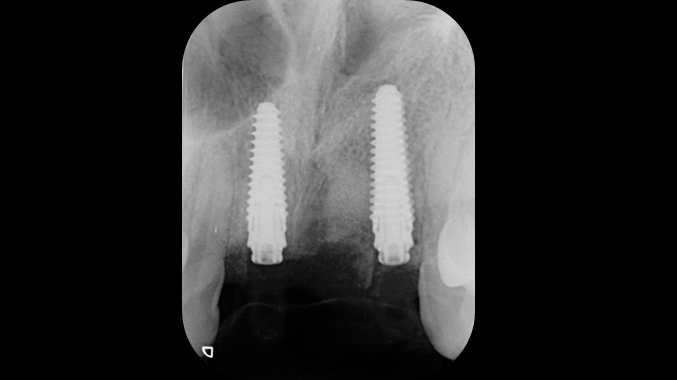

Clinical case: Patient-centered approach: treatment strategy for Root Membrane Technique & delayed implant placement

- Courtesy of Dr. Yoshiharu Hayashi, Japan -

Socket Shield Technique, anterior esthetics, maxillary anterior, esthetic, esthetics, delayed implant placement, socket preservation, AnyRidge, Root Membrane Kit, Root Membrane Technique, Partial Extraction Therapy, PET, esthetic zone, fuse abutment, Dr. Yoshiharu Hayashi,#11,#21,#22

AnyRidge implant system, fuse abutment Root membrane kit, PET Kit